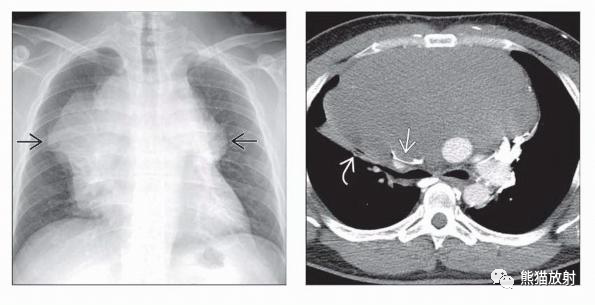

(左) 原发性纵隔T淋巴母细胞NHL,前纵隔巨大、不均质肿块,伴有中心坏死,左侧胸腔积液。

(右) 弥漫性大B细胞NHL伴纵隔受累,冠状PET/CT显示颈部、胸部、腹部和盆腔广泛的FDG明显摄取的肿大淋巴结。与原发性纵隔NHL相比,弥漫性NHL更有可能表现为广泛性疾病。

(左) 弥漫性大B细胞NHL纵隔受累,NECT可见血管前和左侧内乳淋巴结增大和左侧中度胸腔积液。

(右)同一患者,心旁间隙多发肿大淋巴结,双侧胸腔积液。注意,尽管病变广泛,但本病例的前纵隔病变不如原发性纵隔NHL明显。